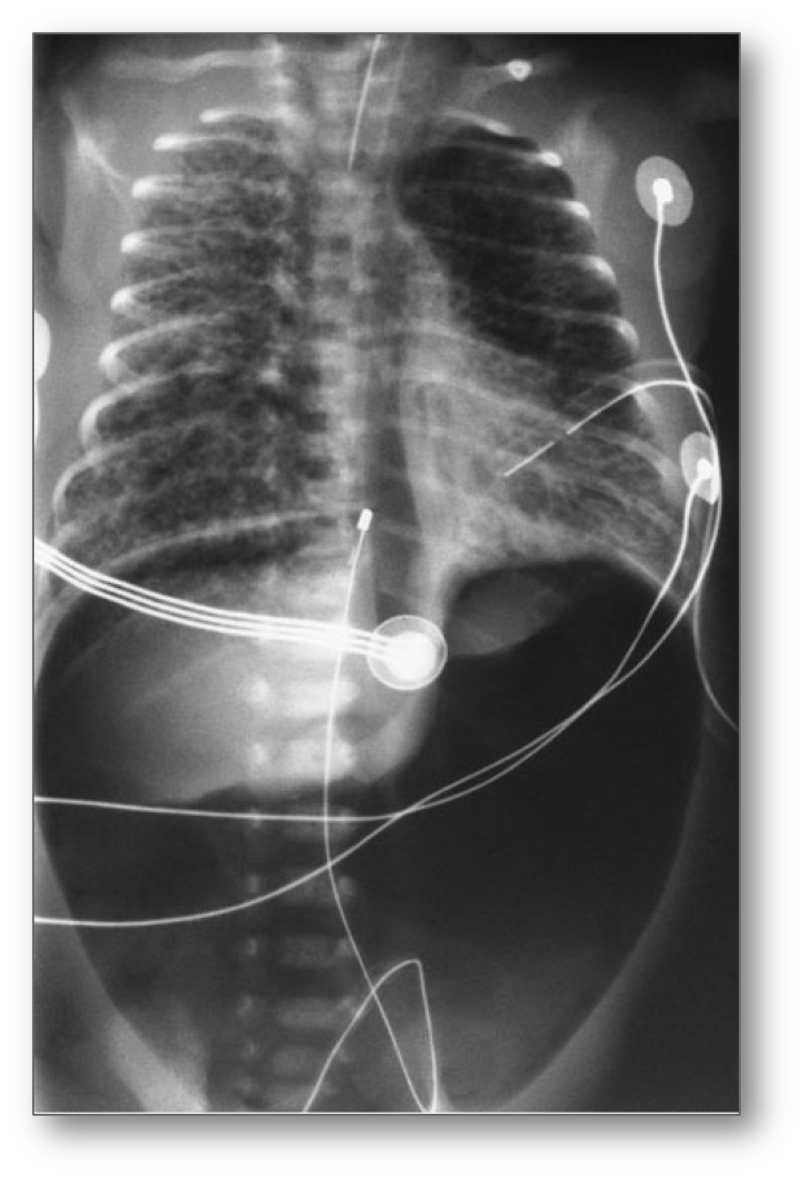

Tension right pneumothorax In Case of Large Pneumothorax

The mediastinum and heart may be pushed to the other side, absent of breath sounds on the ipsilateral side, shifting of cardiac impulse to the contralateral side.